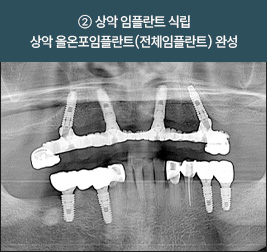

[ 임00님 80세 (여) ]

기저질환으로 고혈압이 있으며,

내원 상담하시어 상악 올온포풀아치(전체임플란트)로

원데이 보철장착한 환자분이십니다.